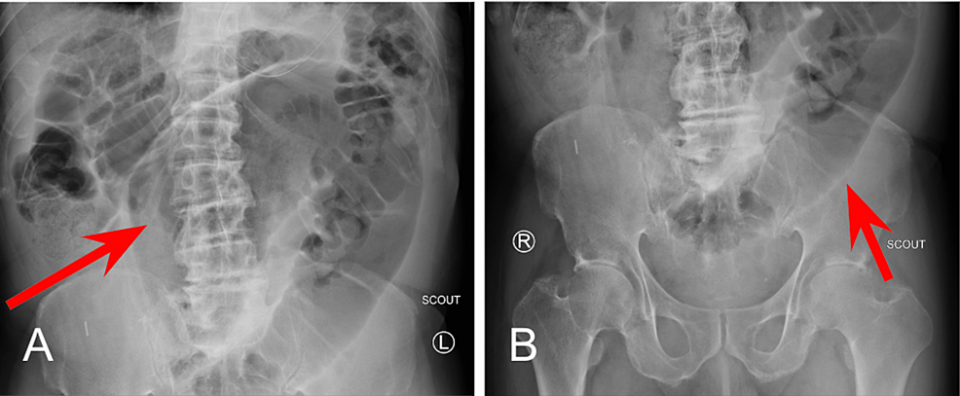

A small bowel series was performed and revealed delayed transit of contrast through the small bowel and dilated loops of the large bowel without enteric contrast, which was concerning for obstruction. Plain radiographs of the upper and lower abdomen prior to the administration of oral contrast can be seen in Figure 1.